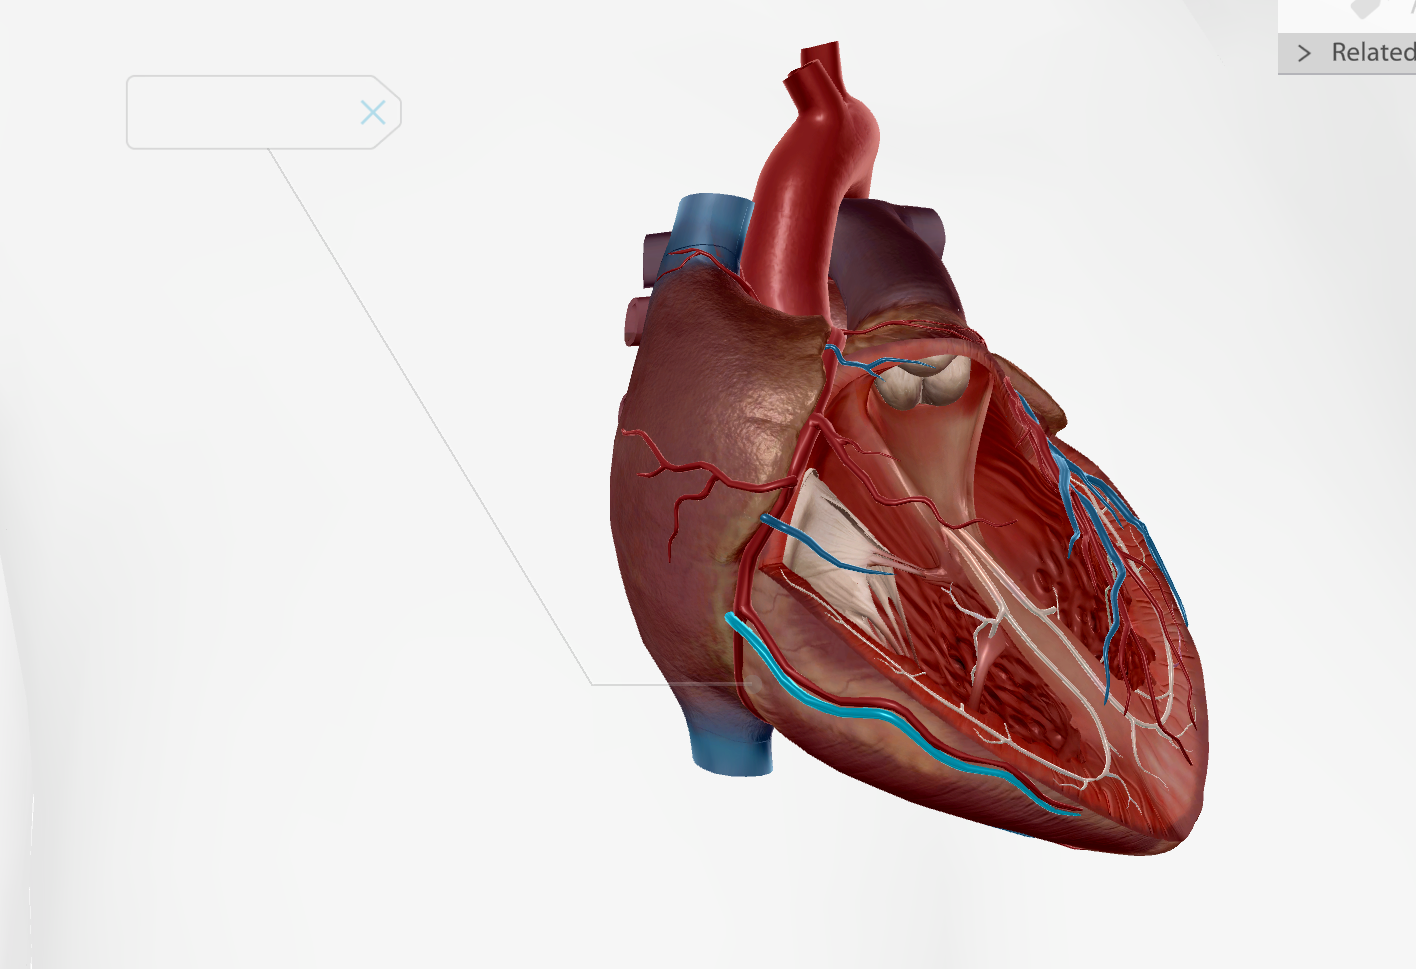

Left Atrium

Right Atrium

Left Ventricle

Right Ventricle

Tricuspid Valve

Bicuspid Valve

Aortic Valve

Papillary Muscle

Pulmonary Valve

Interventricular Septum

Chordae Tendineae